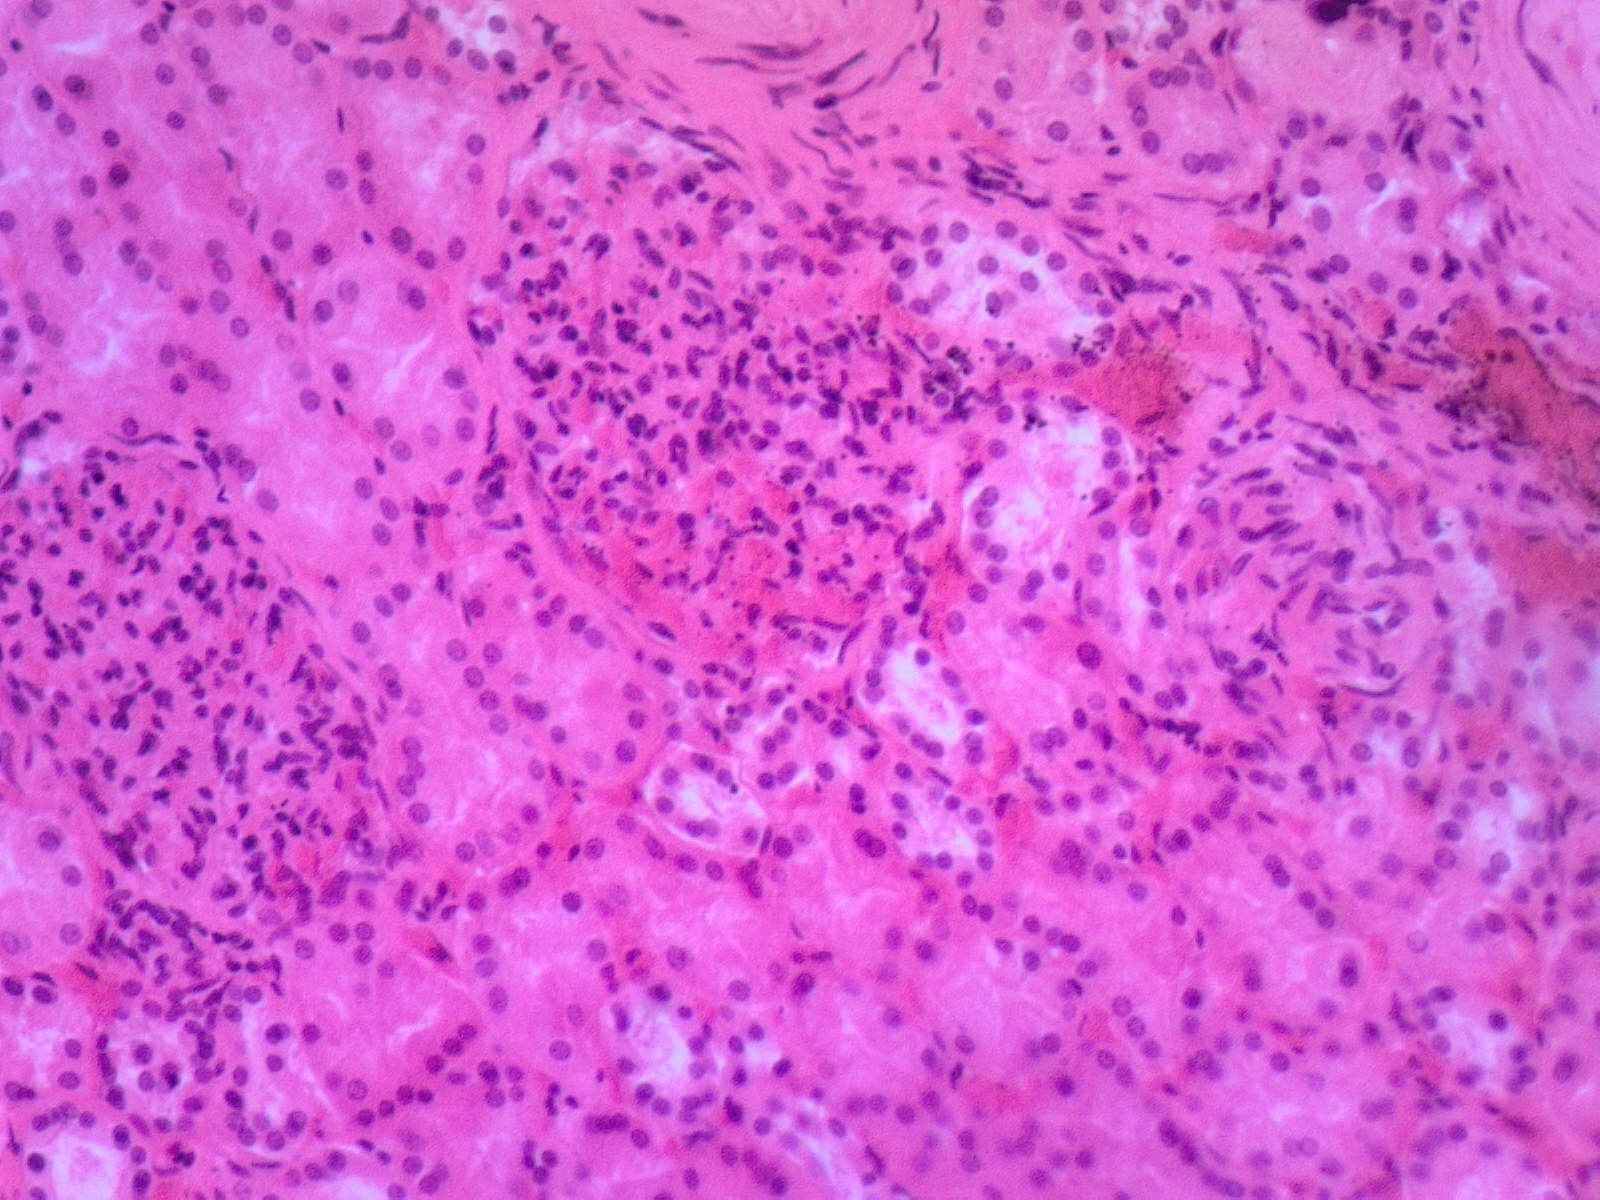

71. Грануляционная ткань

В молодой соединительной ткани определяются мелкие сосуды и большое количество клеток. На большем увеличении среди клеток видны гистиоциты — округлые клетки с несколько эксцентриче­ски расположенным и интенсивно окрашенным ядром и широким ободком цитоплазмы, лимфоциты — круглые клетки с интенсивно окрашенным ядром и узким пояском цитоплазмы, эпителиоидные клетки — клетки с телом полигональной и овальной формы, пузырь-кообразным ядром и широким ободком цитоплазмы; фибробласты и фиброциты — вытянутые клетки с гиперхромным ядром. Среди кле­ток видны полинуклеары, плазмоциты и эритроциты.

Существенные элементы: 1. новообразованные сосуды

2.гистиоциты

3.лимфоциты

4.эпителиоидные клетки

5.фибробласты